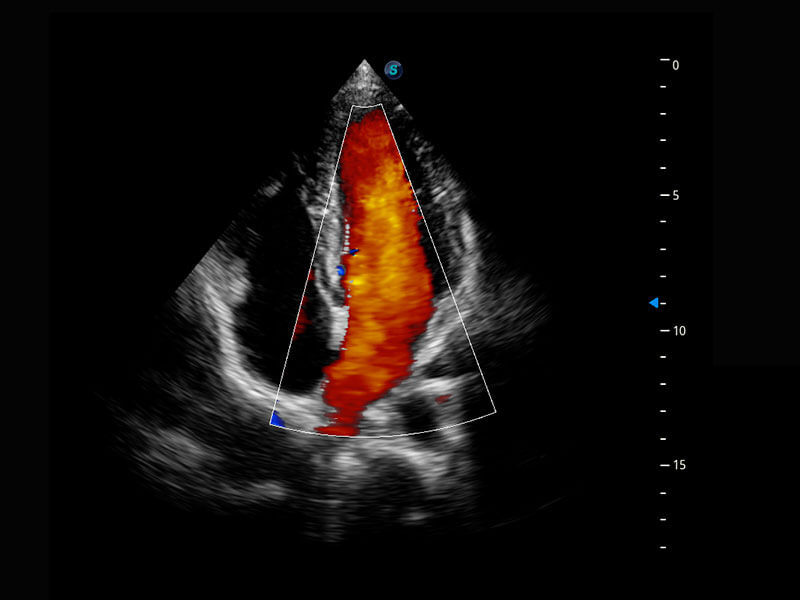

四腔心血流

右室双出口